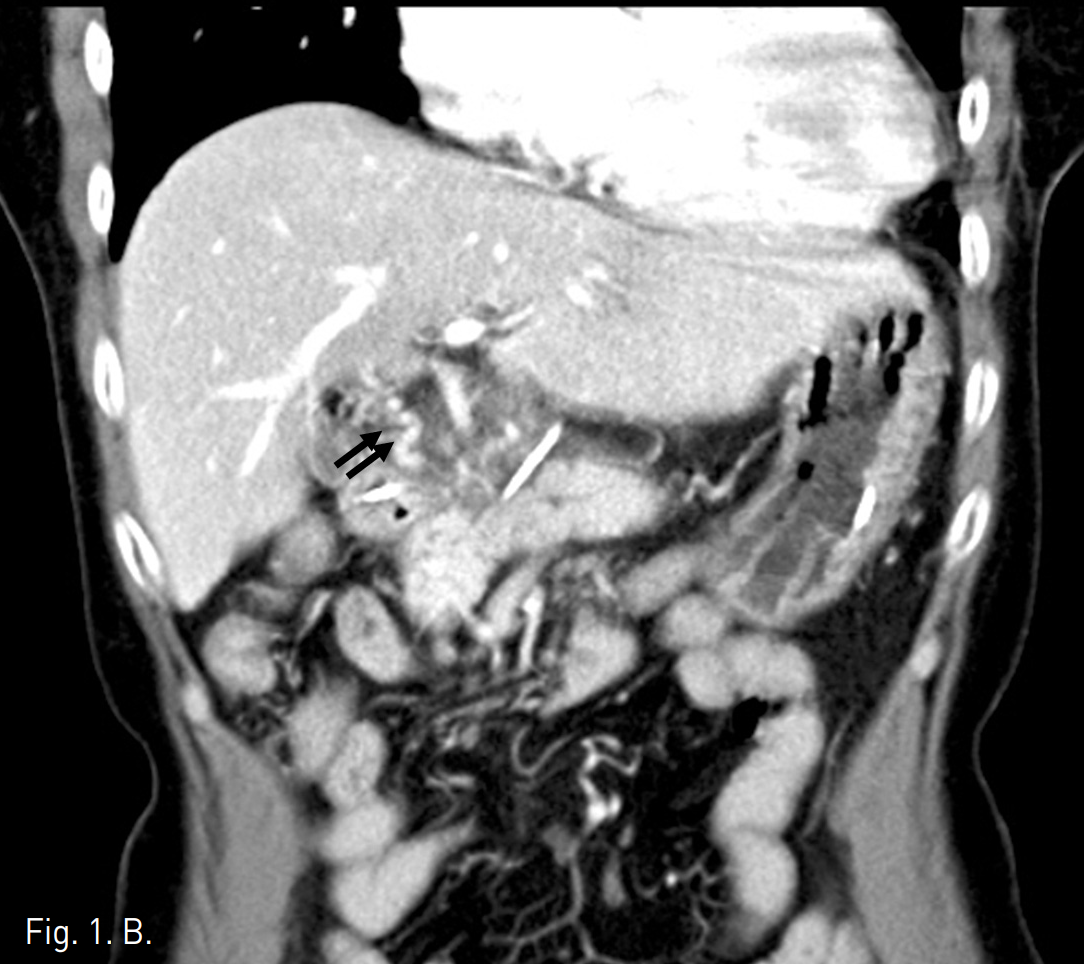

조영증강 복부 CT에서 췌장 경부 상부에 침윤성의 연부조직 음영이 보이며 3cm 정도 크기의 낭성병변이 동반되어 있음. 주문맥은 상기한 연부조직 음영으로 둘러싸여 있고 협착이 있음.주문맥 주위로 해면상변환 (cavernous transformation)이 보임(Fig 1).

Fig. 1

A-B. On CT, soft tissue densities are infiltrated around main portal vein and pancreas. Portal vein (arrow in A) is narrowed and many small collateral vessels (double arrow in B) are around main portal vein. There is about 3cm sized cystic mass close to infiltrative soft tissue densities (arrowhead in A).